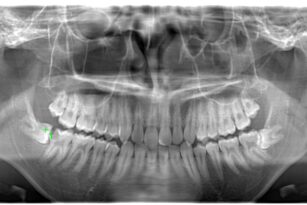

インプラント治療

2025年12月08日

奥歯がない 50代 女性 インプラント治療の症例